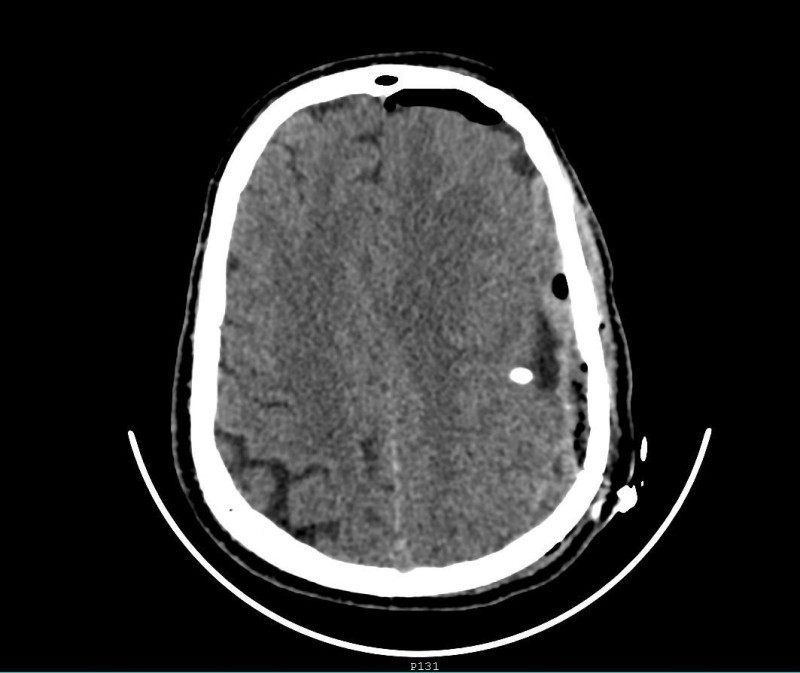

أجرى قسم جراحة المخ والأعصاب بمستشفى الملك عبدالعزيز بمكة المكرمة عملية دقيقة لإزالة الأكياس النزفية في الدماغ لمريض في عقده الخامس بواسطة المايكروسكوب والمنظار بعد معاناته من صداع شديد وفقدان النطق مع ضعف في الجانب الأيمن. وأوضح رئيس القسم الدكتور زهير هوساوي أن المريض قدم لقسم الطوارئ وهو يعاني من صداع شديد وفقدان النطق وضعف الحركة بالجانب الأيمن من شهور عدة، وبعد الفحص السريري والأشعة اتضح وجود أكياس نزفيه بجانب منطقة الحركة والكلام في الدماغ ما استلزم إجراء العملية باستخدام المايكروسكوب والمنظار اللذين يُعدان من أحدث التقنيات العلاجية في هذا المجال، وتمت إزالة التكيسات في المناطق الدماغية كاملة مع المحافظة على منطقة الحركة والكلام. مشيراً إلى أن العملية استغرقت 3 ساعات بمشاركة كل من استشاري جراحة المخ والأعصاب الدكتور محمد المشد واستشاري التخدير الدكتور علي الغامدي والدكتور محسن.